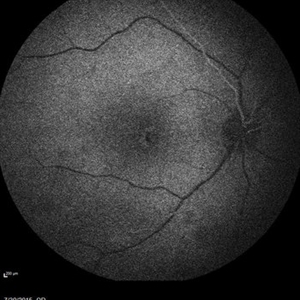

Retinal Dystrophy of 24-Year-Old Male Early FA OD

Nov 25 2015 by Zach Dupureur

Fluorescein angiography of a 24-year-old male. Juvenile retinoschisis on OCT. FA shows outer retinal staining. Could be associated with Goldmann Farve Syndrome.

Condition/keywords: Goldmann-Favre Syndrome, juvenile retinoschisis, retinal dystrophy